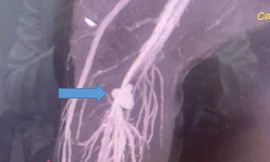

TPO - Đang nằm ngủ, người đàn ông đột ngột ho ra máu lượng lớn, ngay lập tức được gia đình chuyển đến bệnh viện cấp cứu. Các bác sĩ xác định người bệnh bị tổn thương phổi mức độ nặng. Sau khi nhập viện, bệnh nhân tiếp tục ho ra máu, nguy kịch.